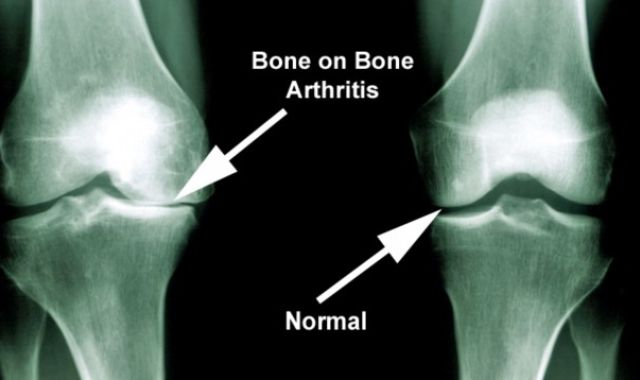

Adult Total Knee Replacements -

Unicompartmental Knee Replacement -